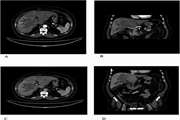

Benign hepatic schwannoma in a patient with chronic hepatitis B infection: A case report 1403/12/26 - 13:43